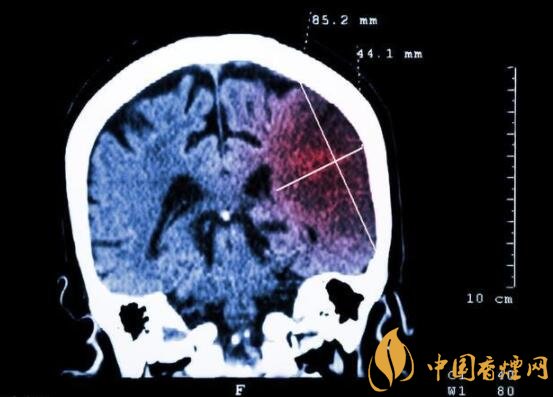

一般而言,急性腦梗塞與長期吸煙有非常密切的聯系。有長期煙齡遇到肢體活動不順,做頭顱核磁共振檢查往往查出一側大腦中動脈閉塞的可能性很高。由此可見,吸煙確實與中風存在一定聯系。

在這當中,吸煙者與不吸煙者做對比,發生中風時間可提前十年。按照每日吸煙1-20支,對比不吸煙者發生中風風險高出3.3倍;每日吸煙20支以上者,比不吸煙者高出5.6倍;30-40歲吸煙者,發生腦梗塞風險比不吸煙者高出5倍;50-60吸煙者,發生腦梗塞風險比不吸煙者高出3倍。由此可見,吸煙量越大,吸煙時間越長,發生中風的可能性越高,特別是多發生在中年